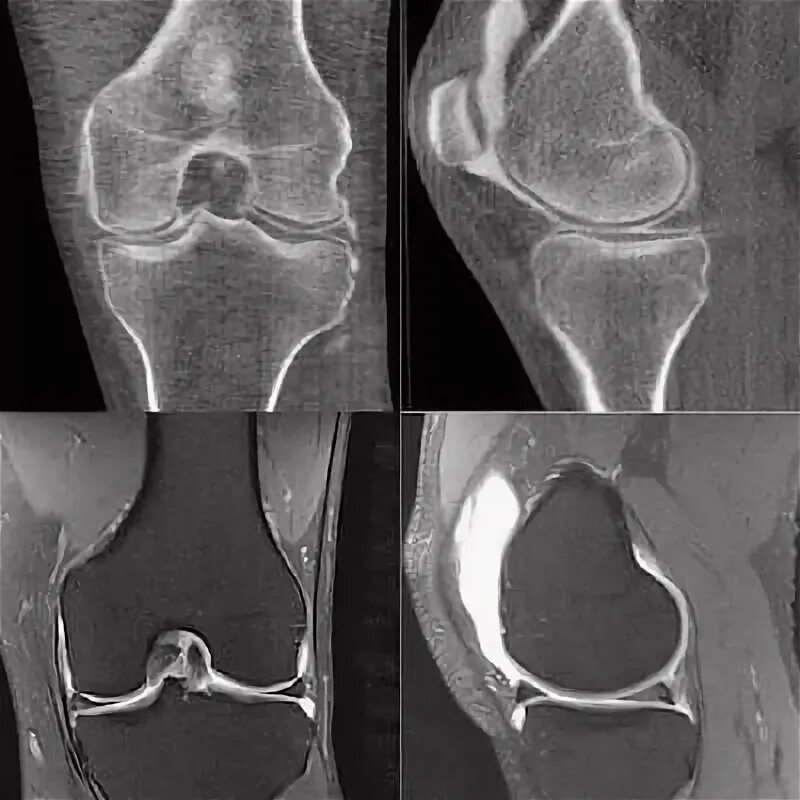

Мрт и кт суставов